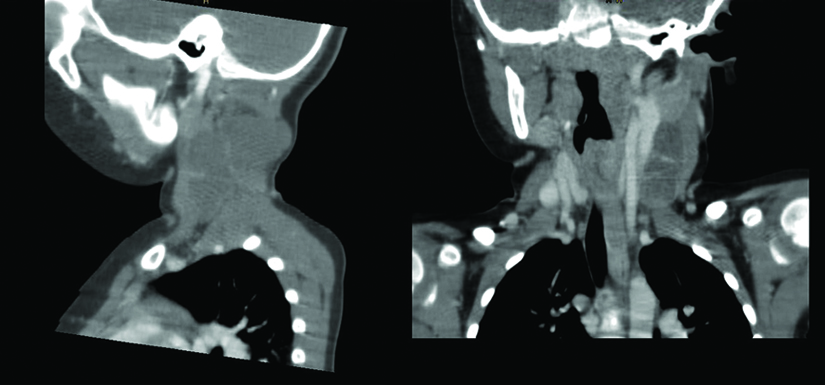

Examenul CT evidentiaza o tumora de dimensiuni mari, de peste 6 cm, care deformeaza intreaga regiune laterocervicala stanga avand raporturi atat cu craniul in regiunea occipitala, cat si cu capatul medial al claviculei.

Ecografia Doppler evidentiaza contactul intim dintre elementele vasculare (artera carotida si vena jugulara - zonele colorate) si tumora cervicala.